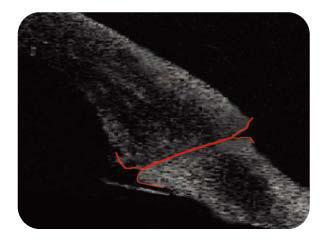

飛秒雷射系統以4D電腦斷層,掃描輔助手術的規劃及手術中全程安全監控。動態4D光學斷層影像,有助術中更清

楚顯示眼組織,使下刀更準確,手術更安全。

4D光學斷層眼睛掃描